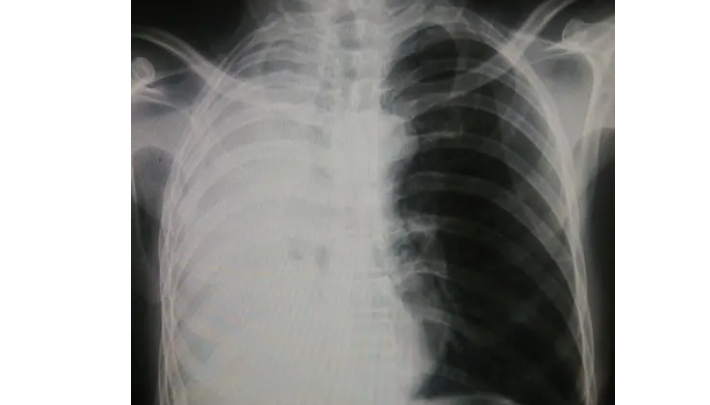

白肺,即肺纤维化,是一种常见的肺部疾病。其特征为肺部组织纤维化增生,导致肺功能受损,表现为呼吸困难、咳嗽及疲劳等症状。许多患者都关心白肺是否可以治愈。那么,能否治愈白肺呢?下面将分别从不同角度探讨这个问题。